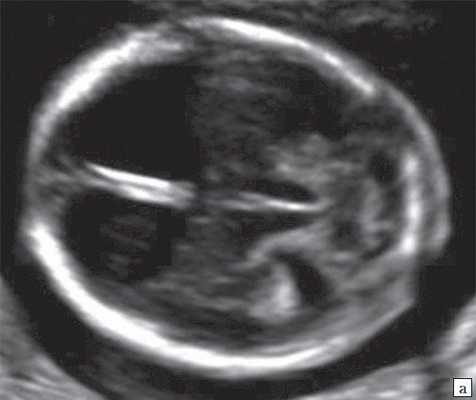

При изучении анатомии головного мозга плода в режиме 2D с применением стандартных аксиальных срезов во всех наших случаях мозжечок выглядел в виде овального образования однородной структуры с поперечным размером, менее уровня 5 процентиля для соответствующего срока беременности. При этом отсутствовала межполушарная выемка и область повышенной эхогенности по срединной линии мозжечка, характерная для отражения червя (рис. 1). На коронарном срезе также обращала внимание округлая однолобарная форма гипоэхогенного мозжечка (рис. 2). Использование трансвагинального подхода позволяло визуализировать дополнительно волокнистые структуры субарахноидального пространства (рис. 2).

Рис. 1. Аксиальные срезы головного мозга плода. Отражена картина однолобарного гипоплазированного мозжечка во всех наблюдениях.

а) Наблюдение 1.

Рассмотрим УЗ-признаки РЭС. Пусковым признаком для ультразвуковой диагностики РЭС плода является получение картины однолобарного и уменьшенного мозжечка. Подчеркнем необходимость при этом применения единых нормативов размеров мозжечка. При выявлении гипоплазии мозжечка дифференциальный ряд включает комплекс Денди - Уоккера и синдром Joubert. РЭС отличается от этих нарушений наличием однолобарного мозжечка, что выражается при УЗИ в отсутствии межполушарной выемки, что дает ровную картину заднего контура мозжечка при стандартном аксиальном срезе и выпуклую картину (dome-shaped) переднего контура при коронарном, что отмечено во всех наших наблюдениях. При описании формы мозжечка в литературе встречается термин "ромбовидная форма" (lozenge-shaped) [3]. У всех плодов в нашем исследовании отмечена гипоплазия мозжечка.

Отсутствие червя выражается однородной гипоэхогенной картиной структуры мозжечка, что видно на стандартных аксиальных срезах при УЗИ. Среднесагиттальный срез (в наших наблюдениях этот срез был получен при трехмерной реконструкции) головного мозга плода показывает гипоэхогенный практически однородный мозжечок, что свидетельствует об отсутствии исчерченности червя, с четко контрастирующей картиной коры. Здесь же видно и отсутствие типичной картины 4-го желудочка с полукруглой формой шатра. Только в наблюдении 4 нами были отмечены фрагменты передних отделов червя мозжечка в проекции стыка водопровода и 4-го желудочка.